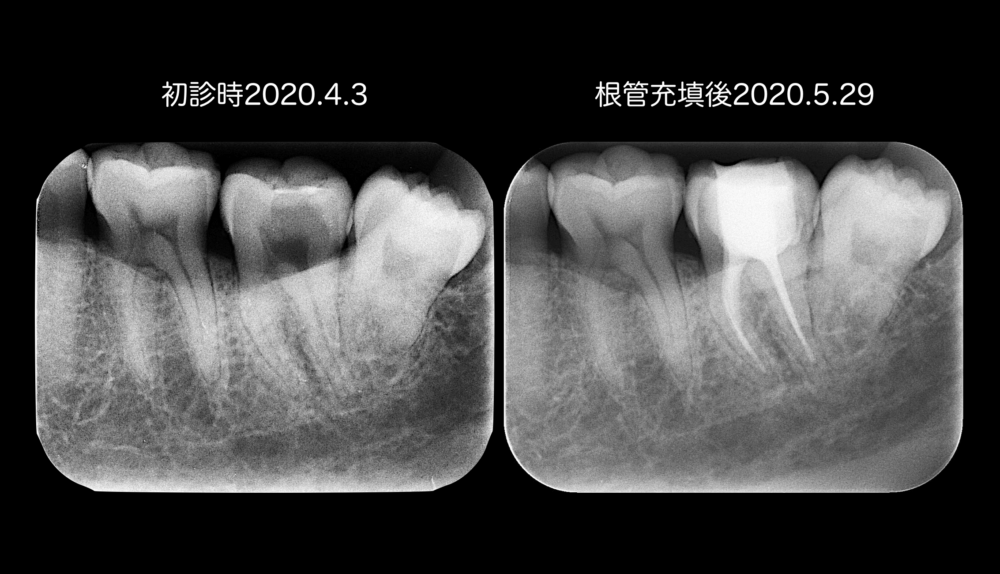

次に、レントゲンをみてみましょう。

初診時のレントゲンで矢印は、穴があいている歯を指します。

黒くなっている部分が虫歯の大きさを表し、口腔内写真での穴よりも大きいです。

以前のブログでお話ししたように、歯髄を残せるかどうかは、虫歯の大きさで決まることもありますが、このケースの場合は、診査の結果、不可逆性歯髄炎だったから、根管治療(拔髄)をしました。